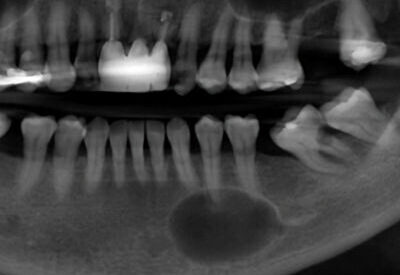

A 9-year-old girl was referred to the oral surgeon by her family dentist because of a “lesion” on her right mandible.